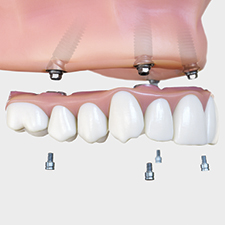

Adapting the Digital Reference Denture Technique for Full-Arch Cases Using a Novel Fixed Attachment System

LOCATOR FIXED Provides "New Tier" of Economic Prosthetic Solution